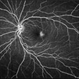

- macular telangiectasia type 2

- Fundus photograph of the left eye of an 62-year-old woman with macular telangiectasia type 2.